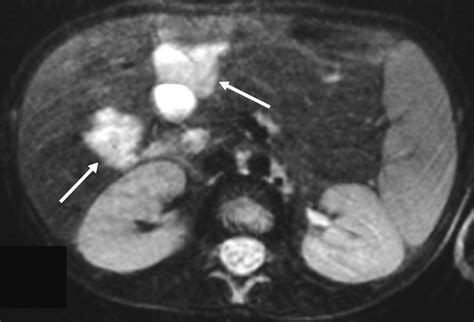

The diagnosis of a Blue Bleb Nevus is typically made through a clinical examination. A dermatologist will visually inspect the nevus and may use a dermatoscope to examine it more closely. A dermatoscope is a handheld device that magnifies the skin and allows the doctor to see the structure of the nevus in detail.

In some cases, a biopsy may be performed to confirm the diagnosis. A biopsy involves removing a small sample of the nevus for microscopic examination. This procedure is usually done under local anesthesia and is generally safe and well-tolerated.